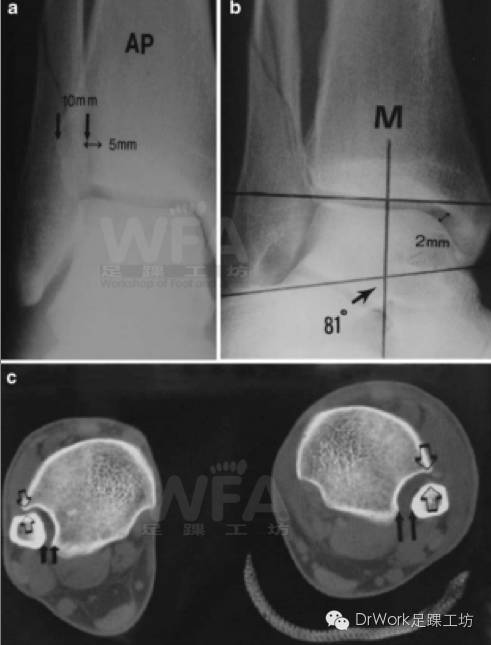

CT复位标准

该患者正位片、踝穴位均正常

• TFCS:5mm

• TFO:10mm

• 胫距角:81o

• 内踝间隙:2mm

但CT显示相对于健侧下胫腓存在分离

CT平扫片上建立坐标系(如图A、B线)

• 测量远端腓骨至B线最近距离(AP)

• 测量远端腓骨至A线最近距离(ML)

• 二维平面上综合反映远端腓骨移位情况

• 更为全面,研究中已逐步应用